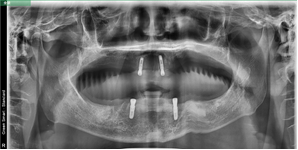

病歷二:

患者,男性,60歲。

主訴:上頜無牙頜,下頜多牙體缺失,余留牙體松動(dòng)不適,進(jìn)食效率低下(困難)明顯,要求治療。

治療方案:完善相關(guān)化驗(yàn)檢查,定制放射導(dǎo)板和種植導(dǎo)板,松動(dòng)牙拔除,并行數(shù)字化全口種植桿卡修復(fù)治療。

術(shù)前片/放射導(dǎo)板定制曲斷片

術(shù)后片/選復(fù)合基臺(tái)(下頜)

桿卡試戴(下頜)/活動(dòng)義齒(上頜)

咬合確定/治療結(jié)束